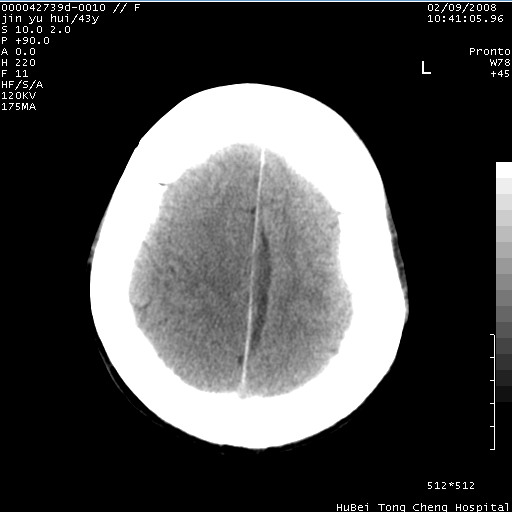

患者 女,43岁。头部外伤26天,经住院治疗,现头痛减轻。申请ct复查,了解颅内情况。

临床诊断:2级脑外伤。

颅脑ct轴位平扫(层厚、层距均为10mm),图像如下:

纵裂旁硬膜下水瘤,左额部头皮肿胀

大脑镰左旁硬膜下血肿慢性期。

大脑镰左旁慢性硬膜下血肿.

大脑镰左旁慢性硬膜下血肿.左额部头皮血肿.